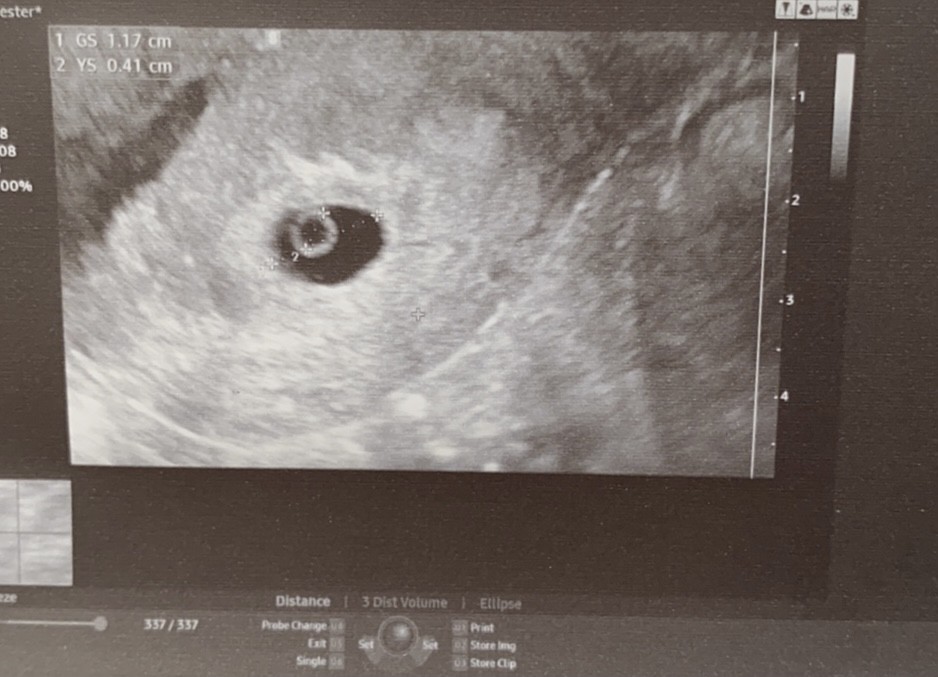

Ciałko żółte za jakiś tydzień powinien juz pojawic się zarodek

Dziwne jest to ze ja miałam tez podobne usg i lekarz już mówił ze bije lekko serce już . To

Możliwe żeby w ciałko zolte bilo

Serce ? Hmmm dziwne . To był 7tydzien

Wstawiam foto